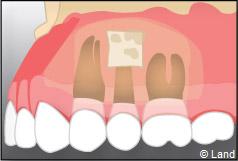

Une fois la dent enlevée, la cavité est nettoyée. En cas d’une dent souffrant d’inflammation, le tissu infecté sera également enlevé.

La fermeture de la cavité s’effectue souvent à l’aide de points de suture servant à réunir les bords de la gencive.

Une prémédication avec des antalgiques et des antibiotiques est très souvent recommandée.